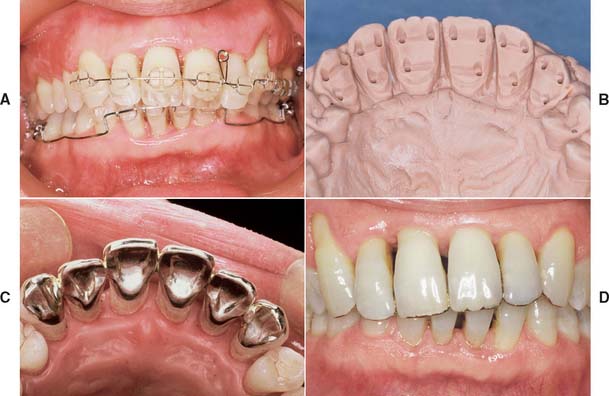

After placement and cementation of a fixed dental prosthesis (FDP), patient treatment continues with a carefully structured sequence of postoperative appointments designed to monitor the patient’s dental health (Fig. 32-1), stimulate meticulous plaque control habits, identify any incipient disease, and introduce whatever corrective treatment may be needed before irreversible damage occurs.

Fig. 32-1 Treatment after placement of multiple restorations. To ensure tissue health and long-term success, proper oral hygiene is mandatory.

To enable the dentist to monitor the function and comfort of the prosthesis and to verify that proper plaque control has been mastered by the patient (Fig. 32-4), an appointment is generally scheduled within a week to 10 days after the cementation of an FDP. The dentist should check carefully that the gingival sulcus remains clear of any residual luting agent that may have been overlooked previously and that all aspects of the occlusion remain satisfactory.

Fig. 32-4 Postcementation monitoring of plaque control is necessary around recently cemented restorations. Poor oral hygiene has led to gingival inflammation (arrows).

Patients with cast restorations should attend recall visits at least every 6 months. Less frequent recall may lead to oversight of recurrent caries or the development of periodontal disease. Patients who have been provided with extensive fixed prostheses (Fig. 32-6) need more frequent recall appointments, particularly when advanced periodontal disease was present. The appointments can be coordinated by the restorative dentist or the periodontist. To ensure treatment continuity, it is imperative to establish in advance who will assume primary responsibility for coordinating recall appointments.

Fig. 32-6 Patients who have received extensive treatment of this nature require more frequent follow-up care.